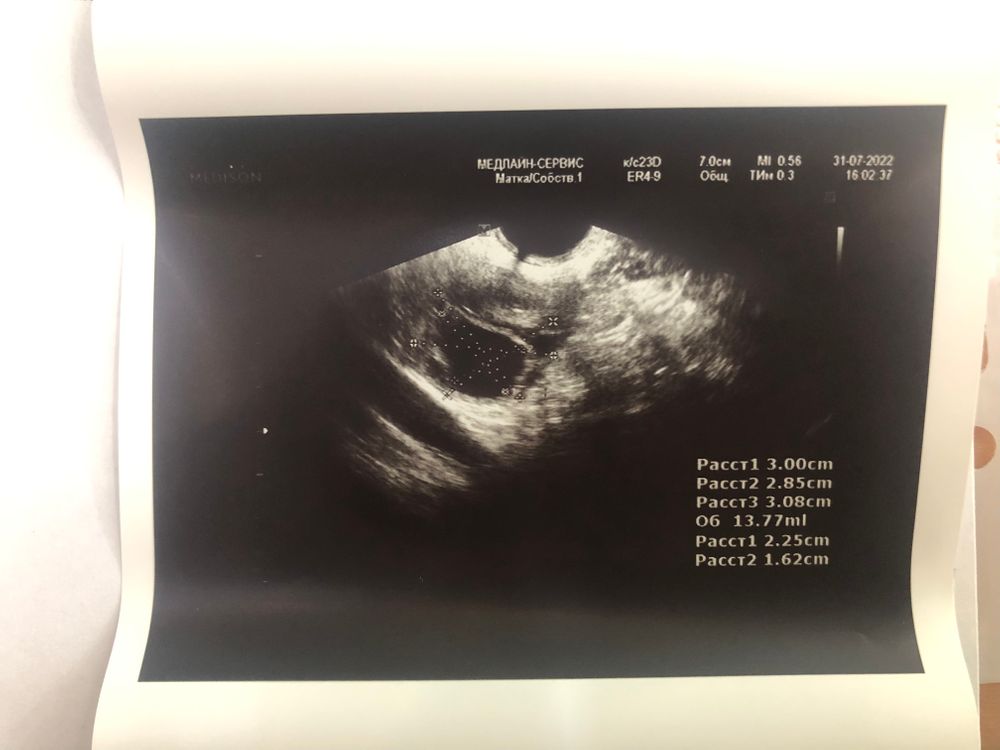

Яна, температуру никогда не отслеживала, не знаю про неё ничего. Я доверяю только УЗИ. По первому УЗИ у вас нашли ЖТ и доминантный фолик. Этот же фолик, как я понимаю, лопнул на 16 ДЦ. Первое ЖТ стало почему-то меньше правда, но тут разные узисты, поэтому погрешность допускаю. У меня в этом цикле тоже двойная О. ЖТ абсолютно разные по величине (разница в О в несколько дней), но какое первое, какое второе не знаю. Эндометрий просто огромный, аж 16 мм😏 И теперь из-за двойной овуляции у меня задержка (тест отрицательный).😐 Предполагаю, что вторая О была на 17-18 ДЦ, вместо 14, поэтому всё и сместилось, ну либо киста выросла. Завтра на УЗИ узнаю.